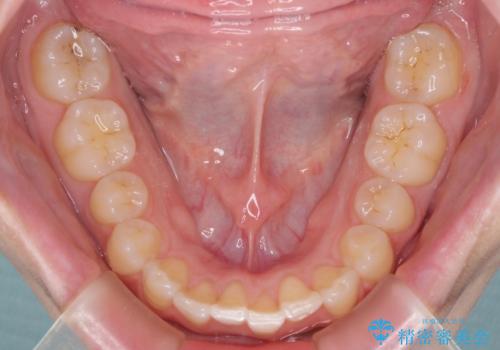

インプラントによる補綴治療とインビザライン矯正

- 抜歯が必要と診断された奥歯を気にして来院された患者様です。

抜歯の上インプラントによる補綴治療を行うこととなりましたが、前歯の叢生も気になるとのことで並行して矯正治療を行うこととしました。

歯列不正は軽微であったので、インビザラインによる矯正治療とし、矯正治療中にインプラント埋入を行う予定としました。

痛みがないので、ボロボロのまま放置していましたが、抜歯後は汚れが溜まりにくくなりスッキリとしたようです。

前歯のデコボコも解消され、ブラッシングが楽になりました。